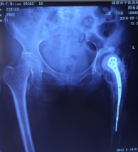

病例1 患者周某,女性,73歲,右髖關(guān)節(jié)置換術(shù)后15年,出現(xiàn)假體松動(dòng)并感染,在我院住院治療,關(guān)節(jié)假體感染翻修被稱為“關(guān)節(jié)外科醫(yī)生的終極挑戰(zhàn)”,老年骨科專家團(tuán)隊(duì)不畏艱險(xiǎn),應(yīng)用301醫(yī)院假體周圍感染翻修的先進(jìn)經(jīng)驗(yàn),采取二期翻修方案,整個(gè)治療分兩步進(jìn)行,第一次手術(shù)取出假體,清除感染,置入帶抗生素的骨水泥占位器,再進(jìn)行6個(gè)月左右的抗感染治療;感染控制后,再進(jìn)行第二次手術(shù),植入翻修人工關(guān)節(jié),并確保感染完全控制;患者經(jīng)過半年時(shí)間的治療,感染得到徹底控制,順利進(jìn)行了髖關(guān)節(jié)翻修手術(shù)。

術(shù)前資料

第一次手術(shù)后

第2次手術(shù)后